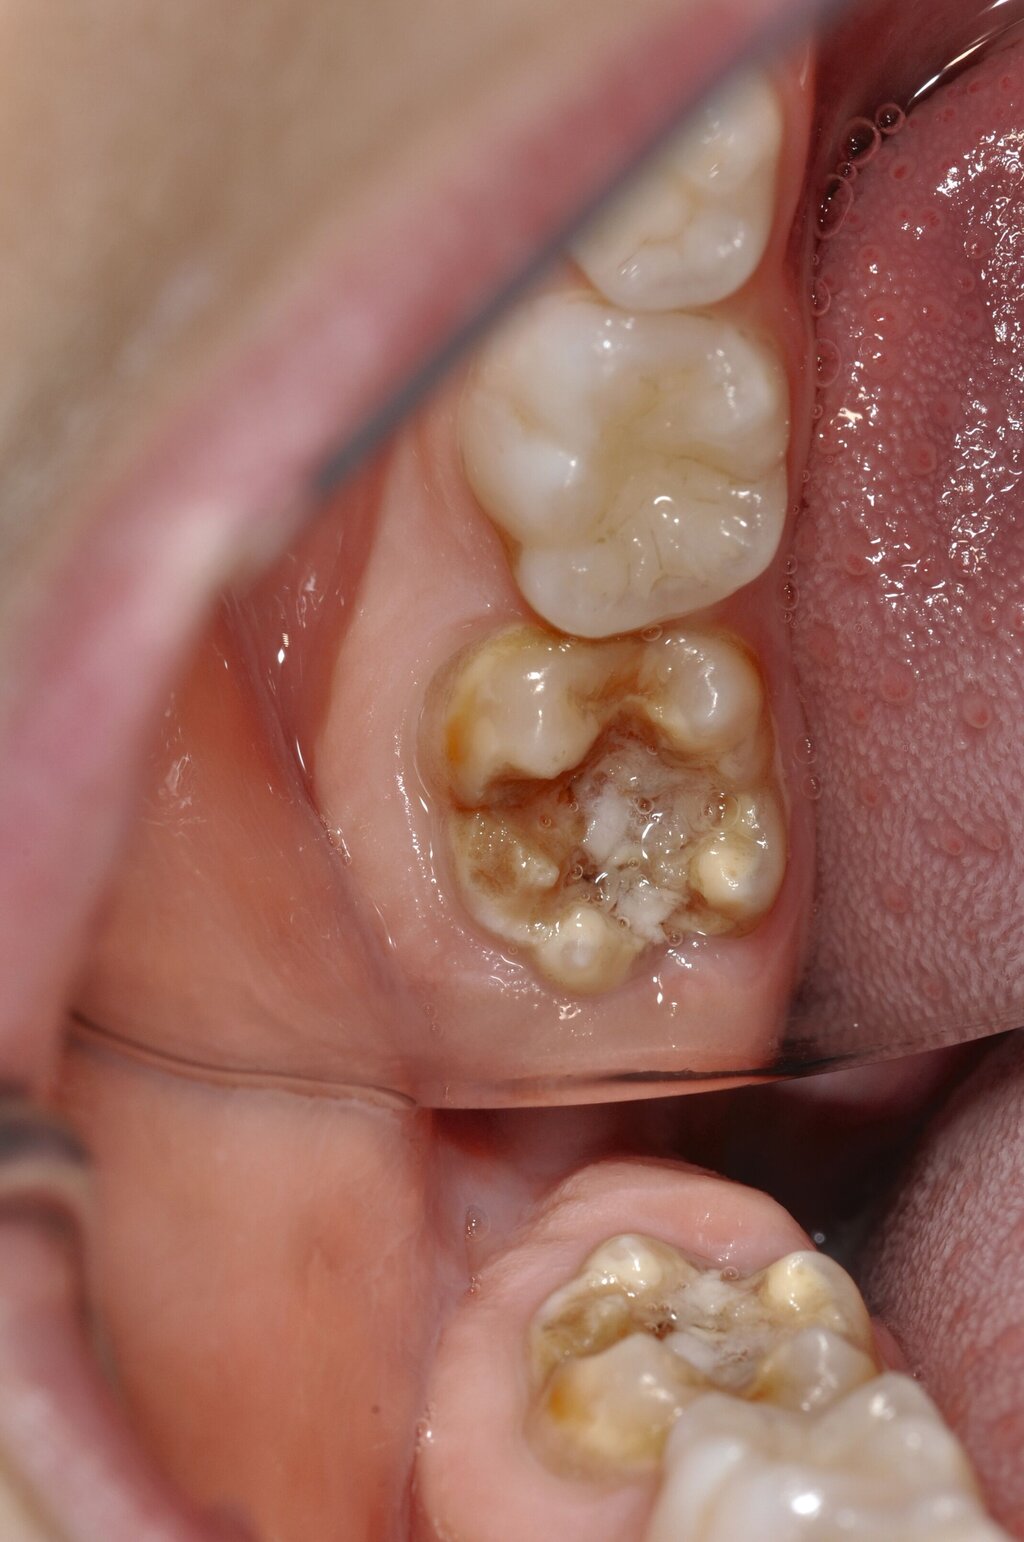

Diese Klassifikation dient als Grundlage für die Therapieempfehlungen. Deutlich wird, dass aufgrund der Symptomatik die Therapie der Zähne höchst unterschiedlich ausfällt. Dass etwa eine Opazität ohne Überempfindlichkeit (Index 1, Abbildung 1) ein anderes therapeutisches Vorgehen erfordert als ein Zahn mit nahezu komplettem Einbruch der Zahnoberfläche und mit Hypersensitivität (Index 4, Abbildung 2), ist offensichtlich.

Die Therapie C hat das Ziel, MIH-Zähne vorübergehend zu versorgen, bis der vollständige Durchbruch der Zähne eine adhäsive Restauration ermöglicht, um die hypersensiblen Zähne zu desensibilisieren oder/und die Mitarbeit für die weitere Behandlung aufzubauen. Vor dem Hintergrund des erhöhten Kariesrisikos dieser Zähne (Abbildung 2) muss durch die Maßnahmen eine Kariesprogression vermieden werden.

Der Behandlungsfall (Abbildung 4d) veranschaulicht die Schwächen des Verfahrens. Wird das Angebot der regelmäßigen Kontrollen nicht wahrgenommen, so droht bei Verlust der Füllung die Kariesprogression. In dem vorliegenden Fall konnte jedoch eine endodontische Maßnahme vermieden und durch die selektive Kariesentfernung die Zahnhartsubstanz weitestgehend erhalten werden.